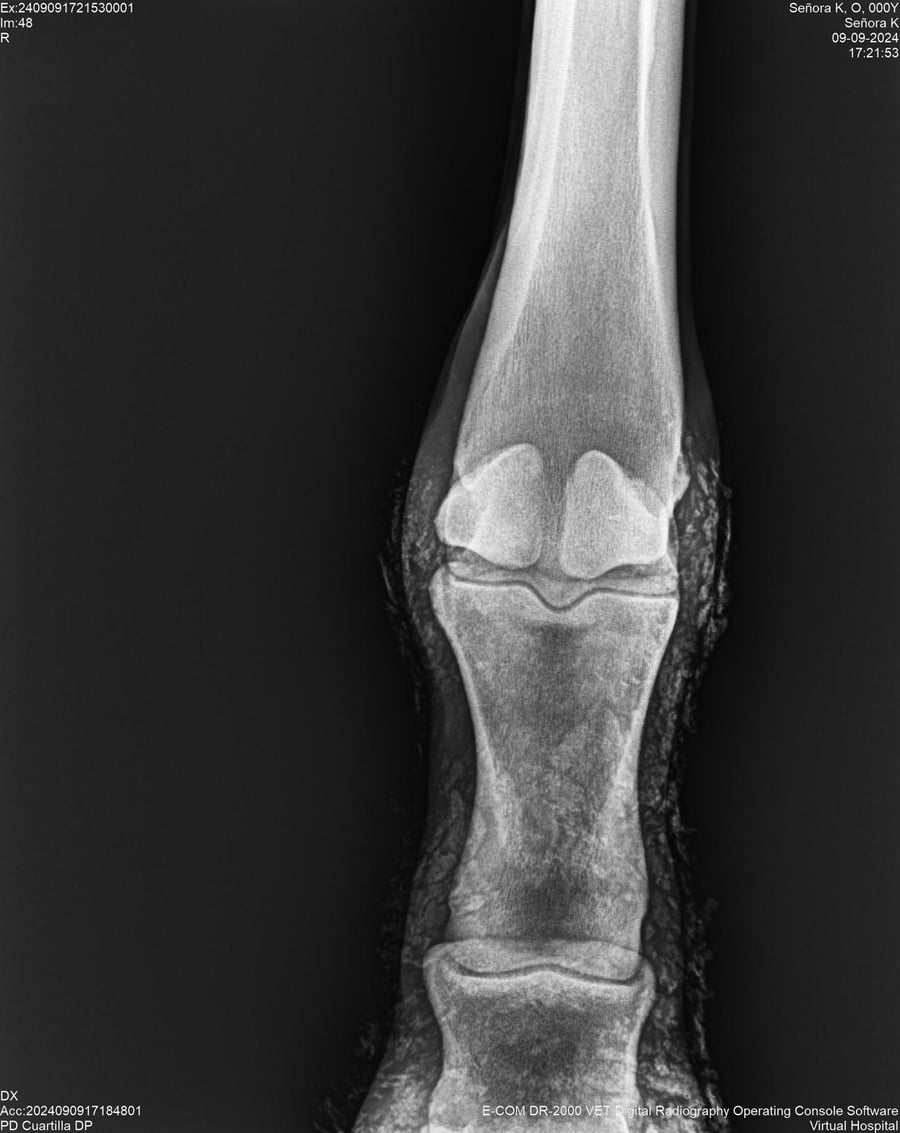

LOTE 44, SEÑORA K

Identificador: #291147-

Generacion 2022